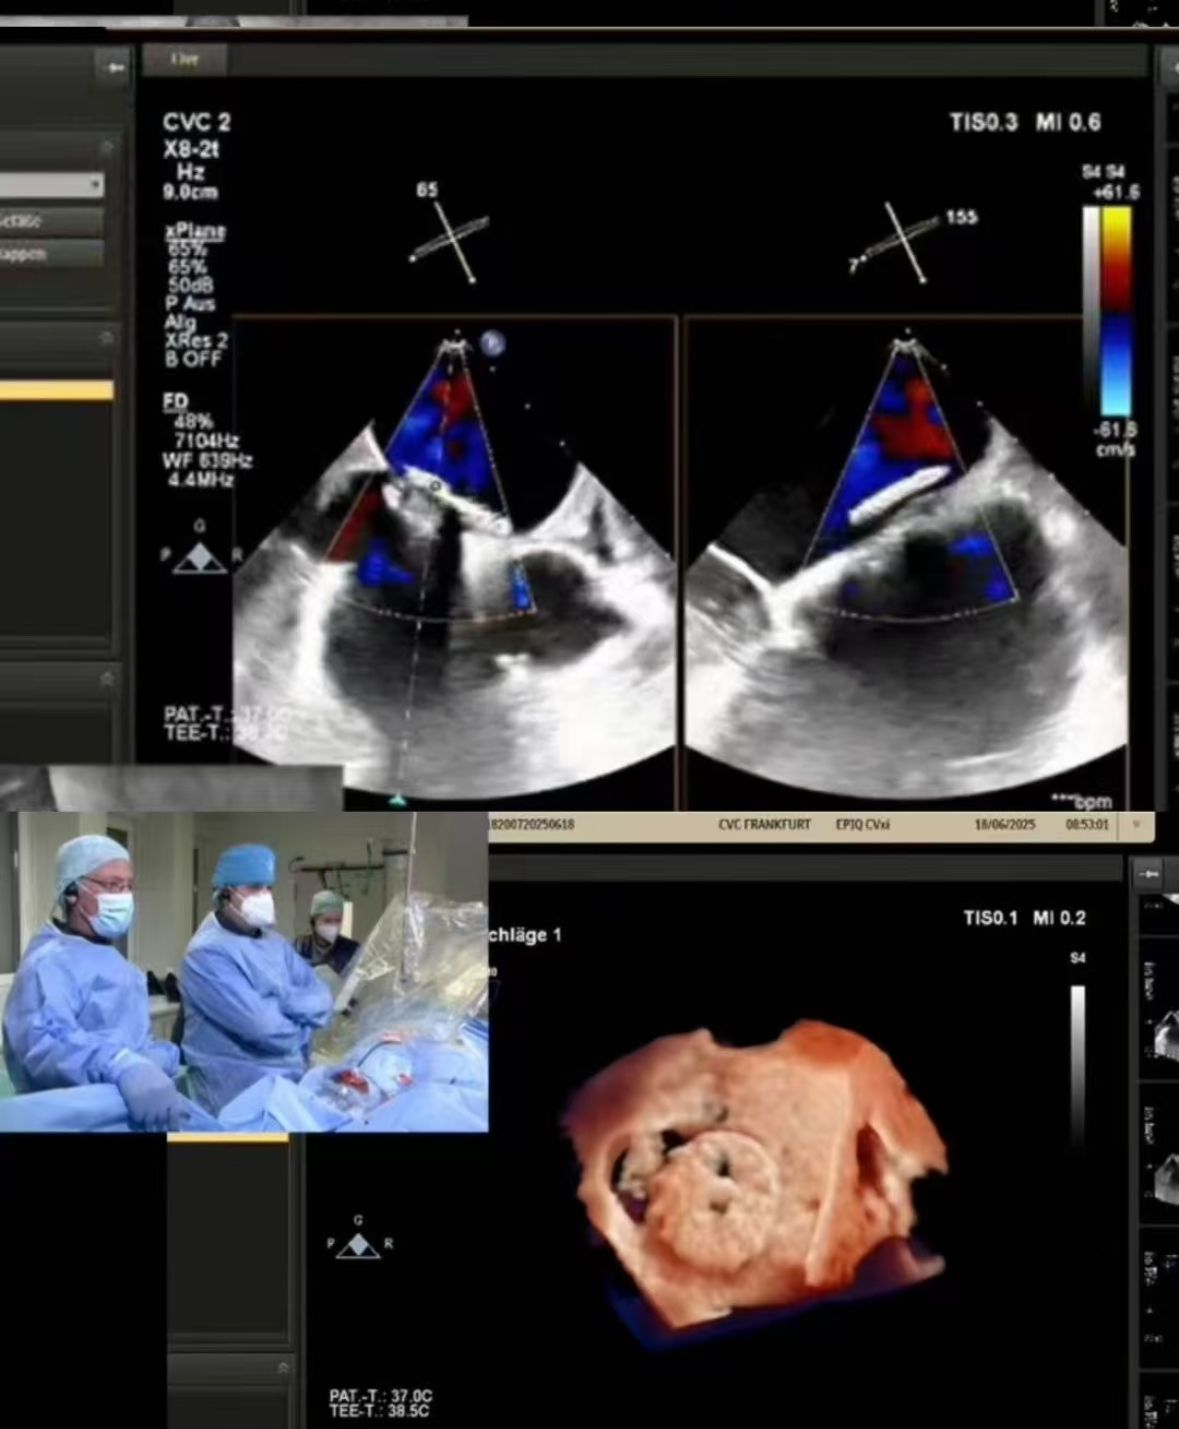

Thrilled to showcase our MemoSorb PFO Occluder – the world's first absorbable device (degrades to water & CO₂ within 1 year) – during a live broadcast from the Blue Room at CSI Frankfurt!

60 yaşındaki bir kadın hastada cvc frankfurt'ta gerçekleştirilen karmaşık bir pfo kapanışı yayınladık:

1. tekrarlayan embolic strokes (2014, 2021)

2. şiddetli nikel alerjisi (metal cihazlar için kontrendikasyon)

3. önceden kapandıktan sonra artık şant

2. hassas kapatma: gerçek zamanlı görüntüleme, zorlu anatomide (pfo tünel fenestrasyonu) mükemmel dağıtımı yönlendirdi.